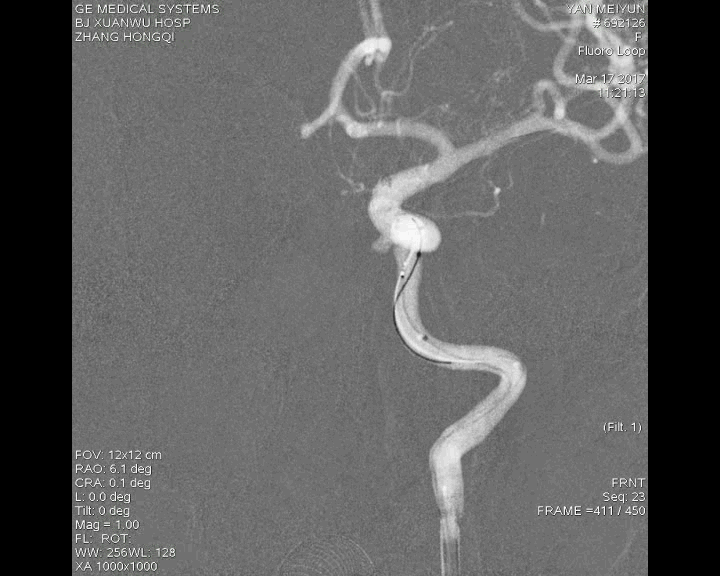

病例一

病例二

病例三

病例四

病例五

病例六

病例七